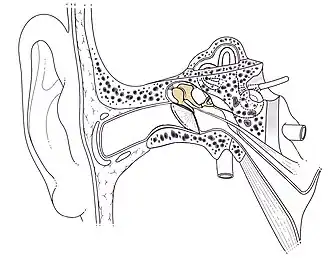

Anatomie fonctionnelle

L'étrier est le dernier des trois osselets formant la chaine des osselets, dont le rôle est de transférer et d'amplifier la vibration sonore, du tympan à l'oreille interne. Il reçoit les vibrations de l'enclume, et va ainsi transmettre cette vibration aux liquides de l'oreille interne via la fenêtre du vestibule, dans laquelle s'insère sa base.

L'otospongiose est une pathologie occasionnant une ostéodystrophie de la capsule otique, entrainant une fixation de la platine de l'étrier dans la fenêtre du vestibule, ce qui provoque une surdité de transmission.

Son traitement chirurgical, la stapédectomie ou stapédotomie consiste à retirer l'étrier et à le remplacer par un piston, venant se fixer classiquement sur la branche descendante de l'incus, et dont l'extrémité médiale est en contact avec le liquide de l'oreille interne.

Galerie

Place de la chaîne des osselets dans l'oreille.

Place de la chaîne des osselets dans l'oreille. Prothèse de stapes